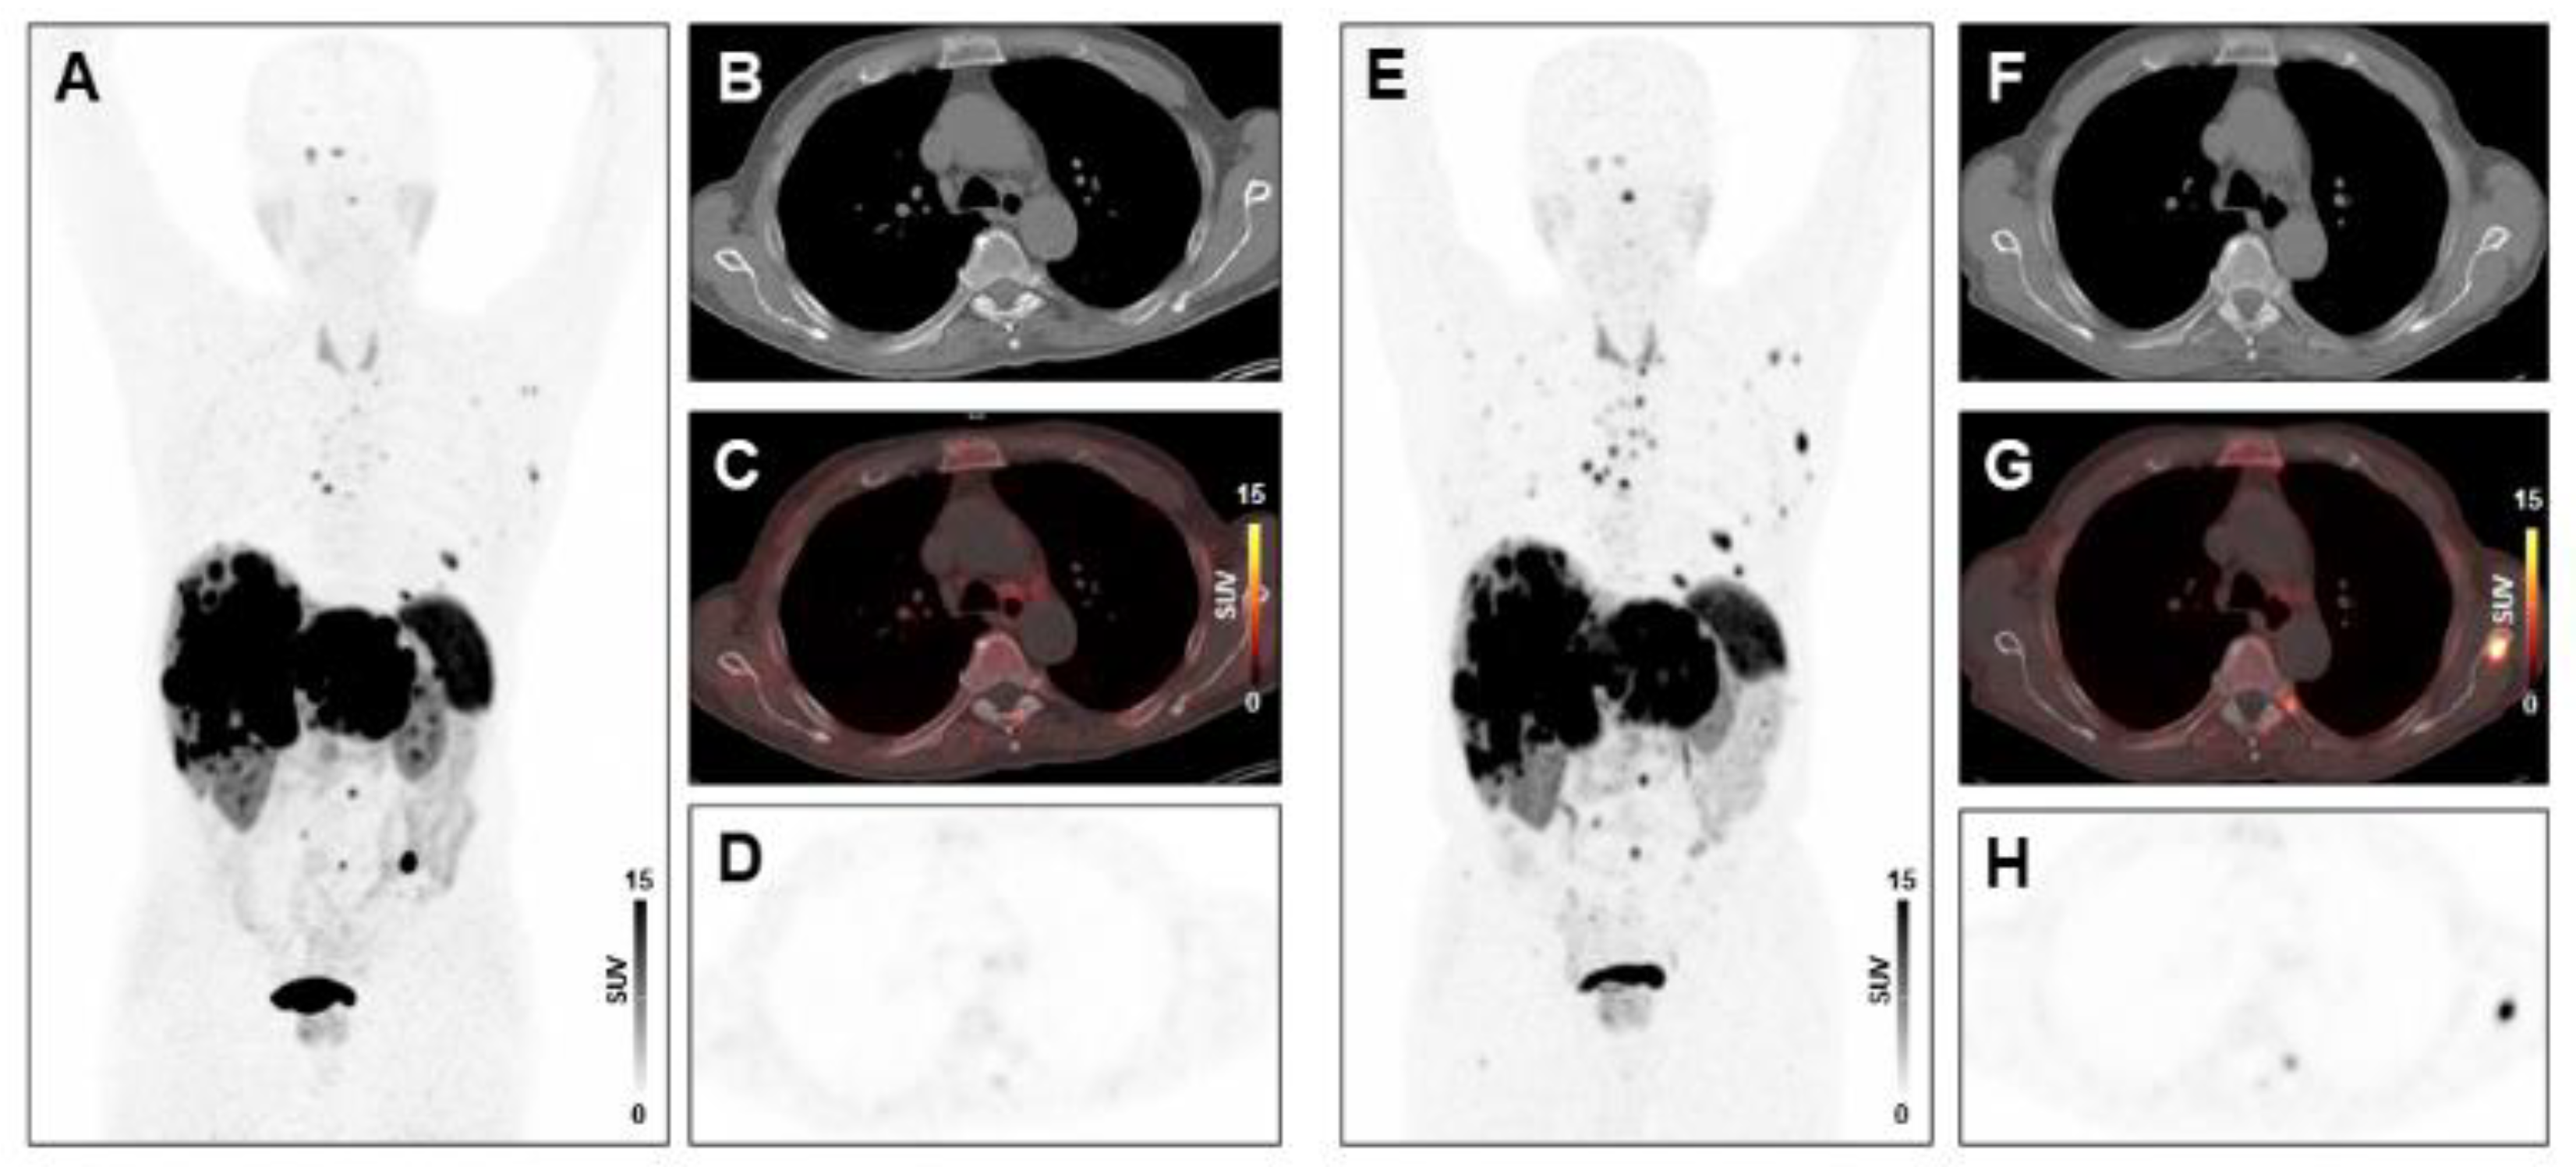

2.3. PET/CT Image Analysis

2.4. Assessment of Treatment Response and Clinical Endpoints